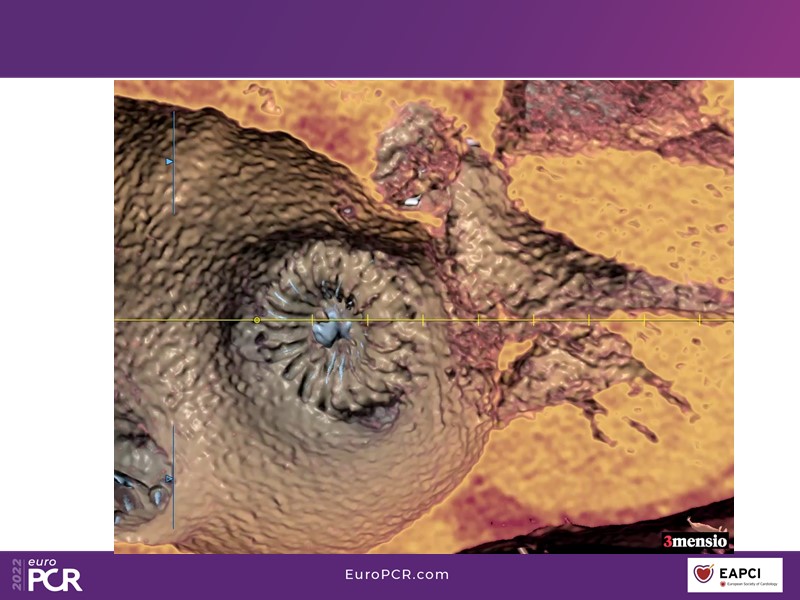

Based on a pre-registered case study of a 68-year-old male patient, DG, who presented with atrial fibrillation, intracranial bleeding on warfarin, and compartment syndrome secondary to bleeding from warfarin, this EuroPCR 2022 session will allow you to discuss the challenges of treating AF patients with previous intracranial bleed, understand the role and functioning of a heart-brain team, and showcase the safety of Watchman FLX in specific subsets of patients.